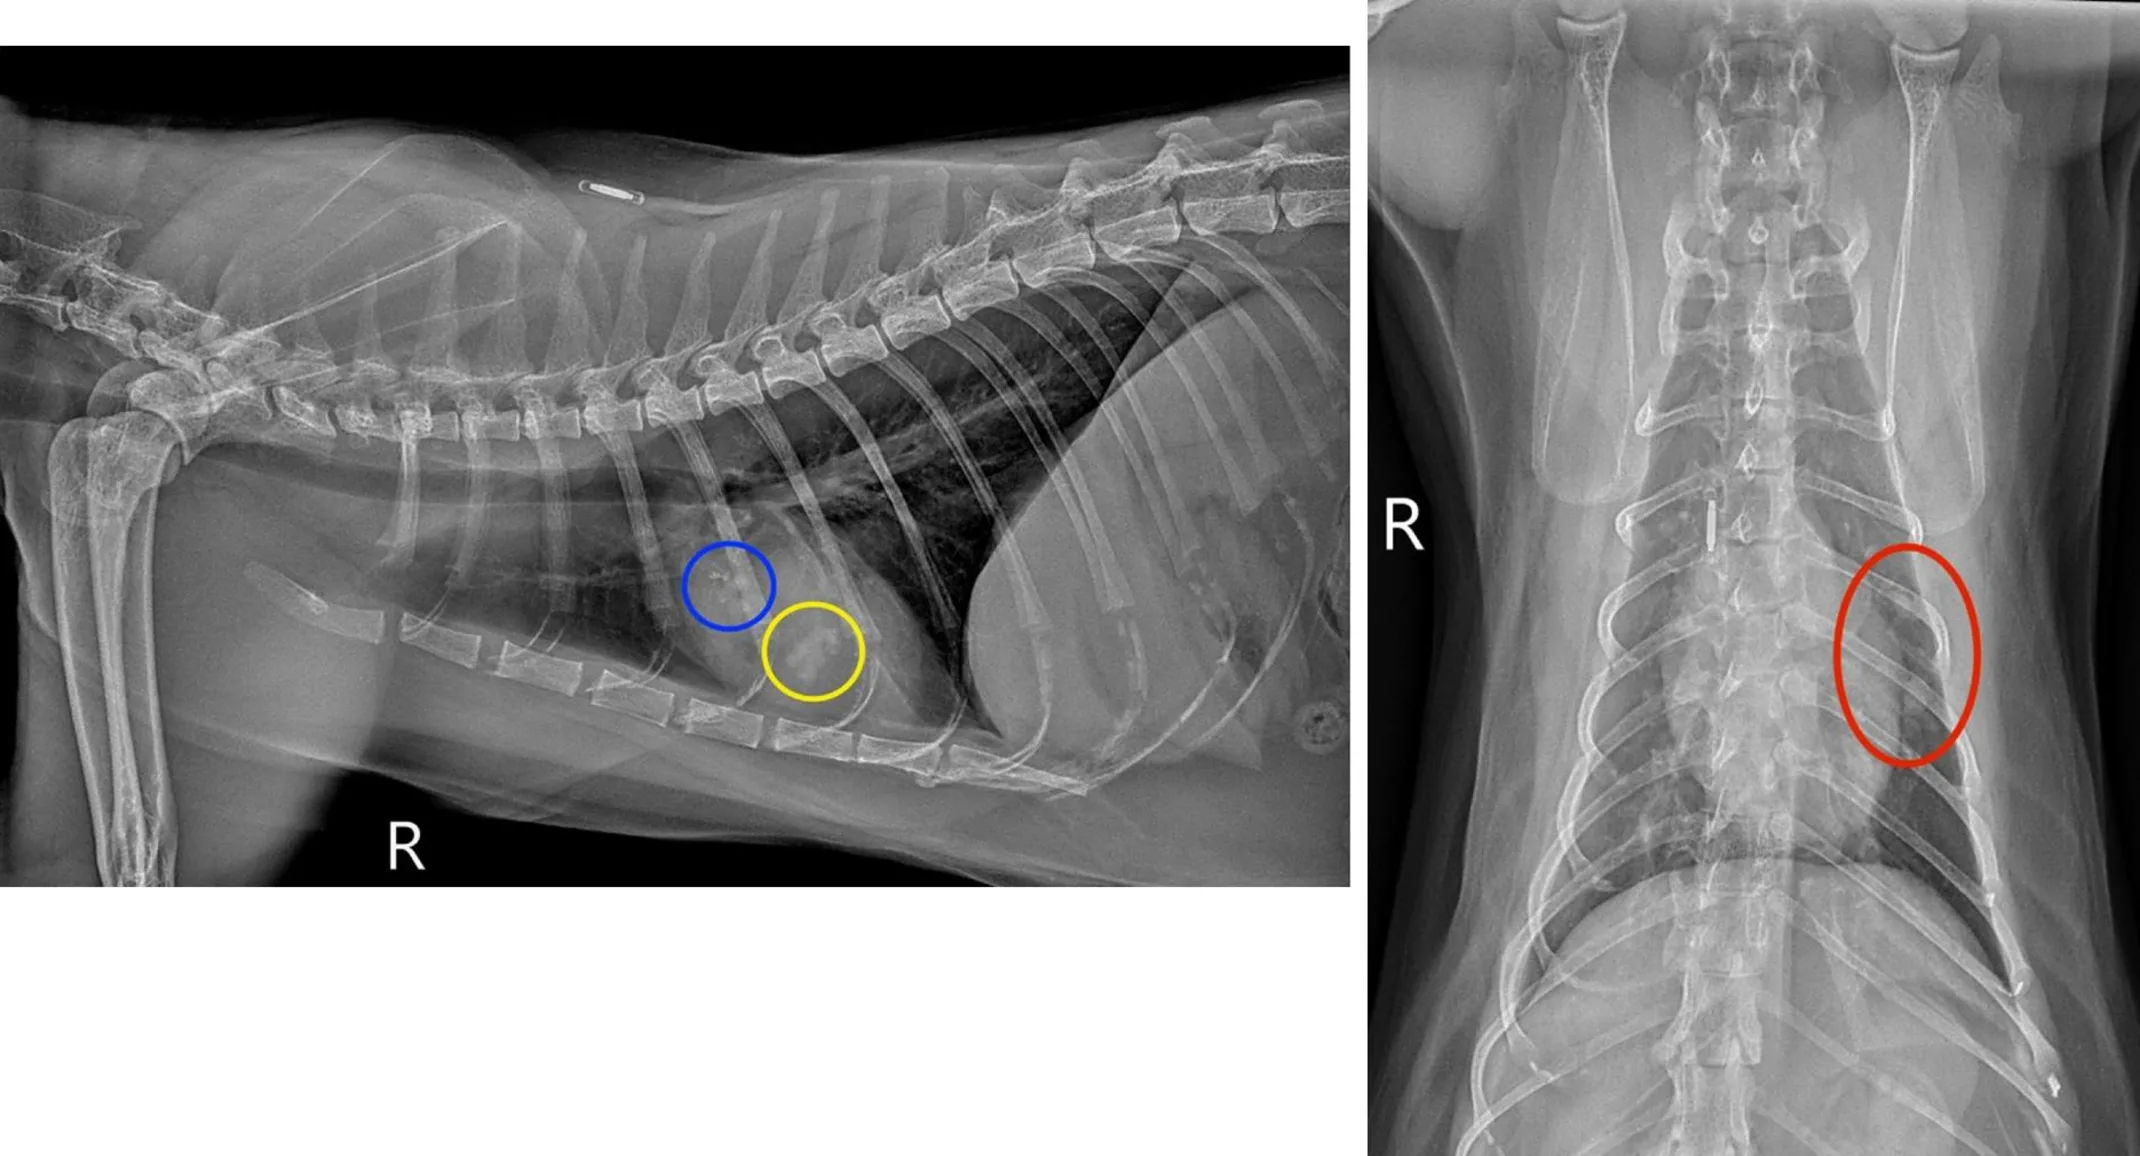

A 12-year-old male neutered domestic short hair presented for general screening prior to undergoing general anesthesia for an annual dental cleaning, and to re-evaluate a small soft tissue to mineral opaque pulmonary nodule noted in the left 5th intercostal space on thoracic radiographs obtained 5 months prior (encircled in green on the ventrodorsal view below). Differentials for the nodule included a granuloma, osteoma, or, less likely, neoplasia (metastatic vs early primary). The patient has a history of occasional vomiting secondary to presumptive chronic enteropathy and/or chronic pancreatitis, equivocal nonprogressive heart disease based on previous echocardiograms, and rare episodes of coughing. A grade II/VI left systolic heart murmur and mild periodontal disease were identified on physical exam.

A multilobulated, mixed soft tissue and mineral opaque lesion (circled in blue) measuring 1.0 x 0.5cm is in the plane of the left cranial lung lobe on the right lateral view, partially superimposed over the 5th ribs and the heart. A second multilobulated, but primarily soft tissue opaque lesion (circled in yellow) measuring 0.6 x 0.9cm is also identified on the right lateral view, located in the 5th intercostal space caudoventral to the first described lesion. Both lesions have a linear branching and nodular appearance that creates a “tree-in-bud” pattern. On the ventrodorsal view, both lesions are in the region of the left cranial lung lobe (circled in red), which is in a similar location as the pulmonary focus seen on prior thoracic radiographs. A mild diffuse bronchial pattern was also noted.

Based on the appearance of the left cranial lung lobe lesions and concurrent mild bronchial pattern, lower airway disease (feline asthma vs chronic bronchitis), bronchial plugging, and broncholithiasis/peribronchial gland mineralization were strongly prioritized over other differentials, such as neoplasia. To further evaluate these findings a sedated, non-contrast thoracic CT was performed immediately following the radiographs.